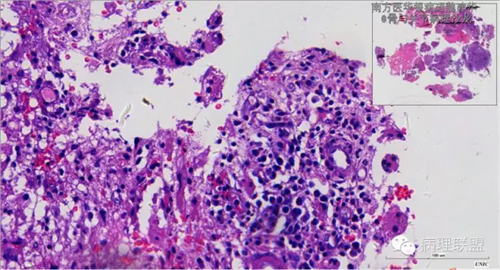

来源于组织细胞的相似性骨病ECD vs RDD 看图说话

病例由南方医华银病理魏建华提供,致谢。